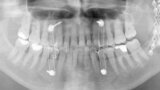

Fig. 1: Situation after multiple mandibular fractures on the left side.